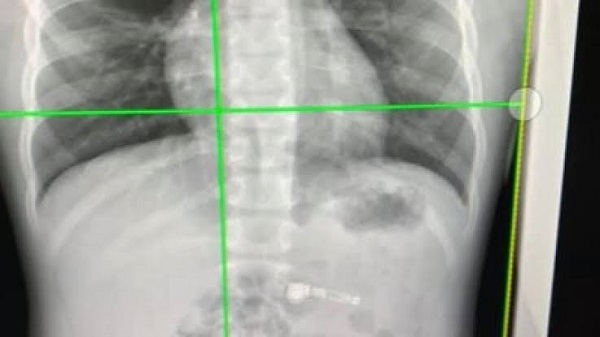

അറ്റ്ലാന്റയിലെ ചിൽഡ്രൻസ് കെയർ ആശുപത്രിയിൽ പ്രവേശിപ്പിച്ച കുട്ടിയുടെ എക്സറെ എടുത്ത് പരിശോധിച്ചപ്പോൾ കുട്ടിയുടെ വയറിനുള്ളിൽ എയർപോഡ് ഉള്ളതായി കണ്ടെത്തി. വിഴുങ്ങിയെങ്കിലും അപകടം ഉണ്ടാക്കും വിധം എവിടെയും തങ്ങി നിൽക്കാതെ എയർപോഡ് വയറ്റിലേക്ക് എത്തിയിരുന്നു. കുറച്ച് ദിവസം കാത്തിരുന്നാൽ ഗാഡ്ജറ്റ് സ്വാഭാവിക പ്രക്രീയയിലുടെ വയറ്റിൽ നിന്നും പുറത്ത് പോകുമെന്ന് ഉള്ളതിനാൽ ഡോക്ടർമാർ മറ്റ് ചികിത്സകളൊന്നും നൽകിയില്ല.